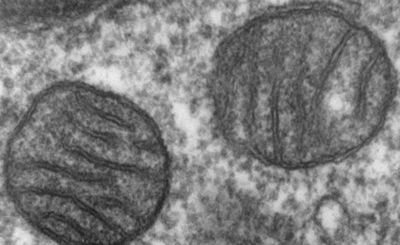

Учёные обнаружили потенциальный способ замедлить старение клеток - New-Science.ru

Старение организма начинается не только на уровне органов и тканей, но и внутри отдельных клеток. Чт